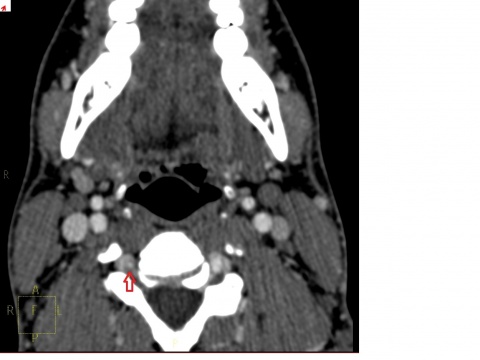

In der koronaren Rekonstruktion zeigt sich in der rechten A. vertebralis

nur ein filiformer Kontrastmittelfluss.

Der Patient stellte sich nach ca. 2 Wochen mit nahezu unveränderter Symptomatik erneut vor. Die wiederholte körperliche Untersuchung ergab nach wie vor den Befund einer Myogelose im Bereich des Musculus Trapezius, jetzt allerdings mit einer rechtsseitigen Betonung. Es wurde die Schmerztherapie um ein schwach wirksames Opiat der WHO Stufe 2 ergänzt sowie eine Physiotherapie mit manueller Therapie und Wärmebehandlung eingeleitet. Acht Tage später stellte sich der Patient notfallmäßig im Krankenhaus vor. Dort berichtete er über eine neu aufgetretene Sehstörung, welche ca. 15 Minuten angehalten habe. Diese wurde von einem Taubheitsgefühl der rechten Gesichtshälfte, welche als Fazialisparese gedeutet wurde, begleitet. Zudem habe er kurzzeitig unter einer Sprachstörung im Sinne einer Broca-Aphasie gelitten. Bei Aufnahme waren lediglich die zuvor bekannten Nacken- und Kopfschmerzen vorhanden. Ein initial angefertigtes Notfall-CCT zeigte einen altersentsprechenden Normalbefund, ohne Hinweis auf eine Ischämie, einen Tumor oder eine Blutung. Die angeschlossene CCT-Angiographie konnte eine im Seitenvergleich schmalkalibrigere A. vertebralis rechts mit Dissektionsmembran nachweisen.